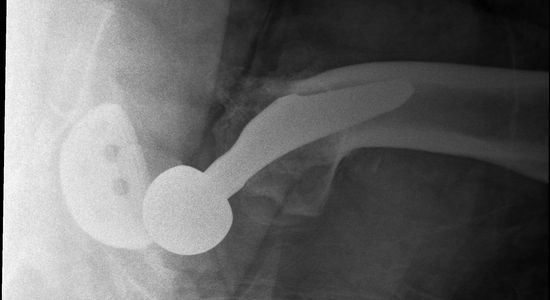

Subsequent spasm of the muscles longitudinally traversing the hip joint leaves the ball sitting behind the rim. The muscle spasm causes superior movement and further wedging of the ball. This can be seen in the X-ray above, and clinically as leg shortening and internal rotation.